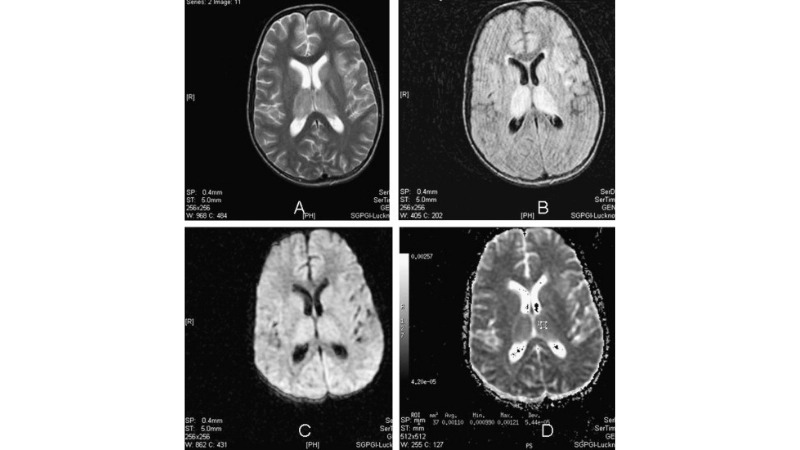

Image description of Murray Valley Encephalitis

Murray Valley Encephalitis is a rare but serious viral infection transmitted by mosquitoes, primarily affecting the brain and nervous system, with potential life-threatening complications.